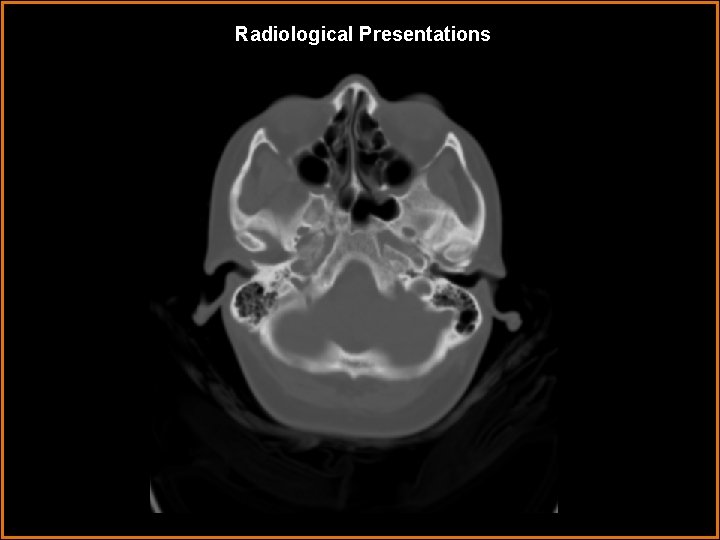

Findings and Differentials Findings: Pre and Post contrast T 1 -weighted images demonstrate enhancing soft tissue within the left cavernous sinus, with extension of the enhancement through the left foramen ovale along the 3 rd cranial nerve. The carotid flow voids are normal. The CT image in bone window demonstrates the foramina ovale to be symmetrical and not expanded. Differentials: • Tolosa-Hunt Syndrome • Sarcoid • Meningioma • Perineural spread into cavernous sinus via V 3 • Infection